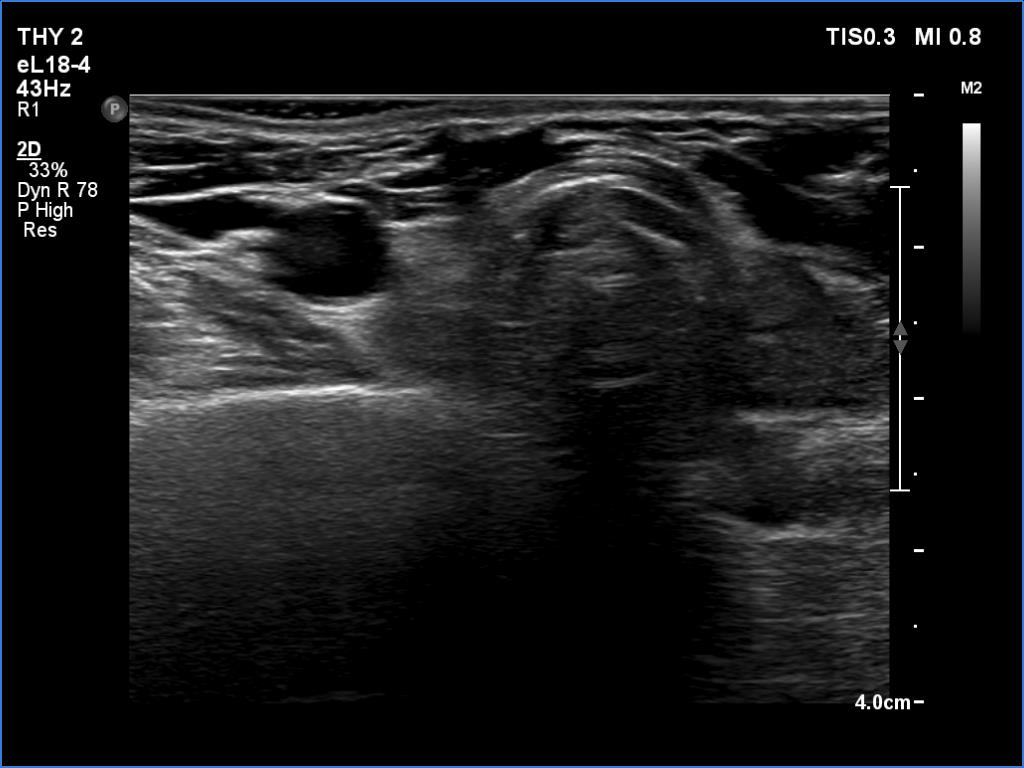

First examination (first row of images):

Clinical data: A 61-year-old woman was referred for evaluation of a suspicious recurrent nodule which was discovered on carotid Doppler examination. The patient was operated on Graves' disease 17 years ago. Histopathology disclosed diffuse goiter.

Ultrasonography. There was a small, moderately hypoechoic remnant according to the resected right lobe while a much larger but still small remnant was found in the left thyroid bed. The latter had an amorphous discrete lesion which presented bright echogenic granules. The lesion was avascular.

FNA was performed from the mass. There were no follicular cells on the smear, only inflammatory cells were found. Our diagnosis was granulation around surgical thread.